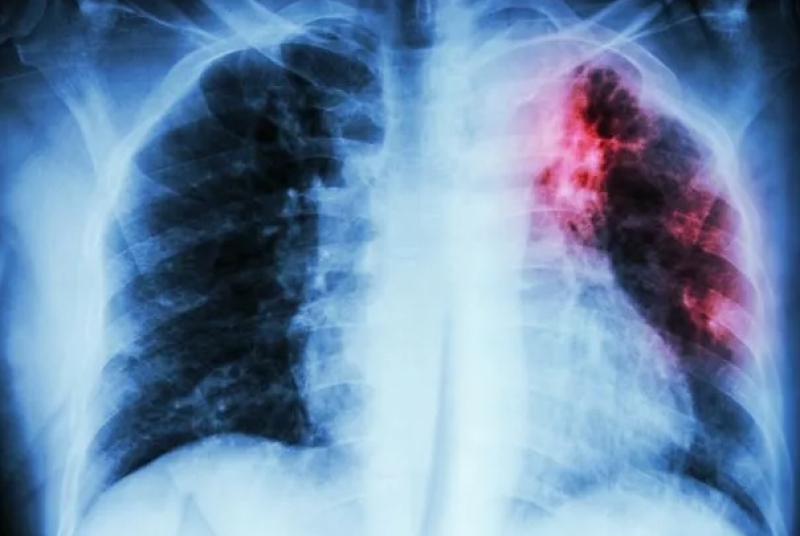

По време на "Седмицата на отворените врати" в периода 23 до 27 юни 2025 г. бяха обхванати 118 лица, изследвани с анкета, физикален преглед, рентгеноскопия на гръден кош, туберкулинов кожен тест – Mаntouх. Резултатите показват, че е открит 1 случай на Туберкулоза на белите дробове и 1 случай на Латентна туберкулозна инфекция. Стартирано е лечение в съответствие с утвърдените медицински стандарти, методични указания и оперативни процедури по данни на д-р Мирена Сапунджиева, областният координатор на Националната програма за превенция и контрол на туберкулозата.

В резултат на изпълнението на Националната програма за превенция и контрол на туберкулоза в България и по данни на МЗ e налице тенденция за трайно намаляване на заболяемостта от туберкулоза - от 23.8 на 100 хил. население през 2014 г. до 13.7 на 100 хил. през 2024 г. Заболеваемостта от туберкулоза в страната по данни на МЗ за 2024 г. представлява 13.7 на 100 000 население, като регистрираните лица с туберкулоза са 913.

За област Силистра заболеваемостта от туберкулоза е с тенденция за трайно намаляване - от 20,68 на 100 хил. население през 2014 г. до 7,4 на 100 хил. през 2024 г.

Регистрираните новозаболели за 2025г. от началото на годината до месец юни са общо 7 случая.